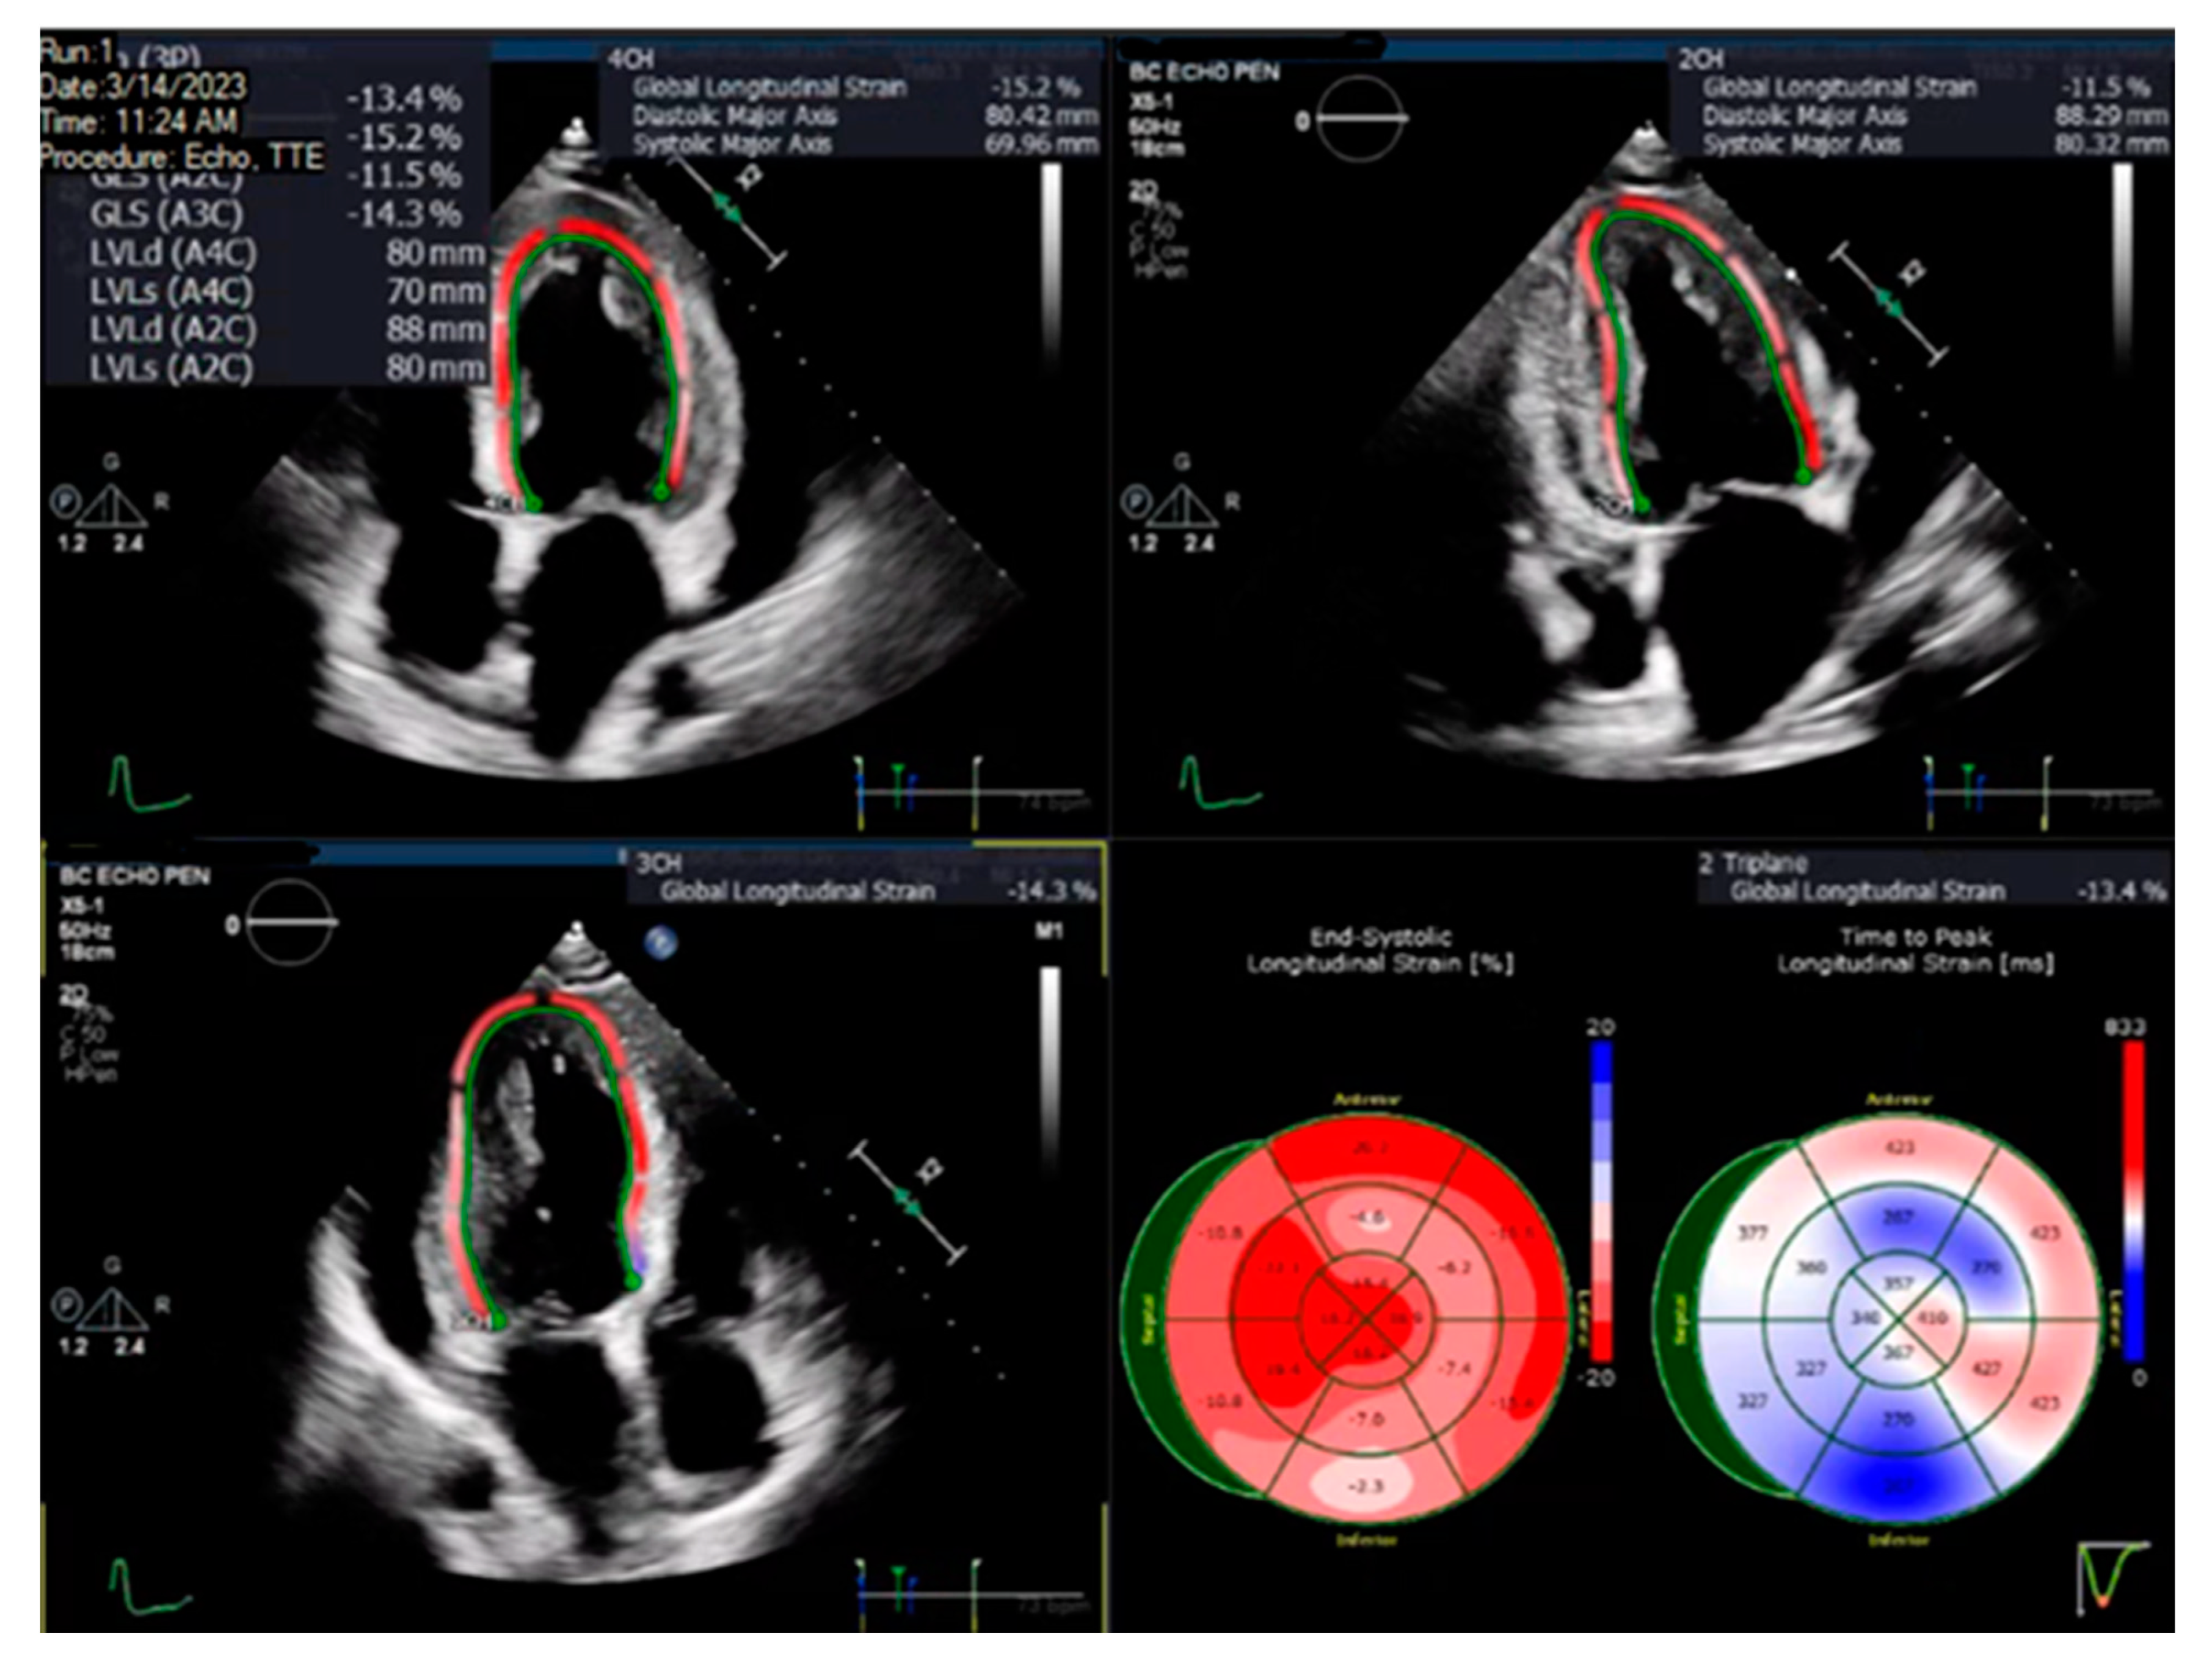

2.3. Echocardiographic Data

| LV GLS (%), mean (SD) | −15.3 ± 3.1 | −16.5 ± 3.1 | 0.01 | −15.1 ± 3.0 | −16.0 ± 5.4 | 0.21 | −15.4 ± 3.5 | −17.7 ± 2.7 | <0.01 |